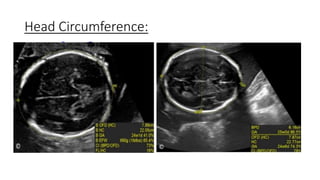

Head Circumference: